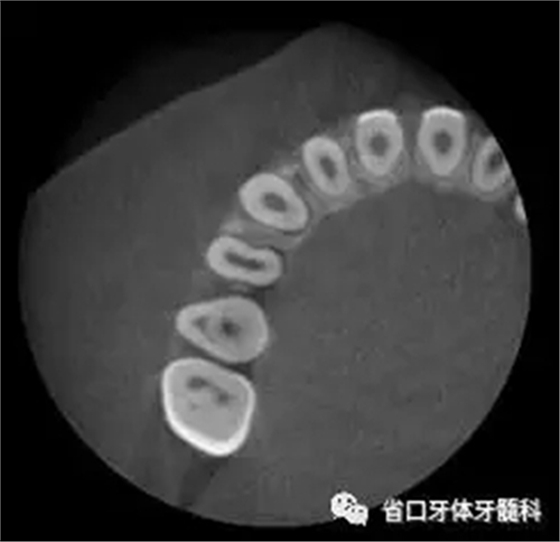

圖3 CBCT(2016-11-13):15由髓腔至根管內(nèi)見團(tuán)塊阻射影像,阻射影中央為透射影,根尖1/3處見根管膨大,腭側(cè)牙槽骨破壞,根尖周低密度影范圍大,上頜竇黏膜增厚。